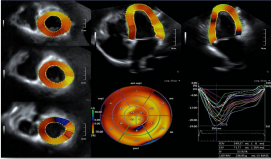

1) 二维/三维室壁运动追踪技术 (2D/3D Wall Motion Tracking)

2) 心脏容积成像